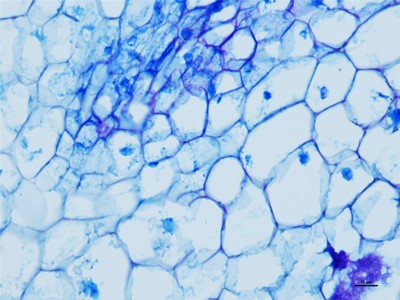

我们要在显微镜底下观察细胞的时候,就得把组织和细胞以及需要观察的东西切片,这些就得控制在厚度大概在1-10微米,这个厚度是最好观察物质的,如果没有在这个厚度之间的切片基本在观察就没有什么颜色。下面陕西依科生物技术有限公司针为大家介绍HE染色的具体操作步骤。

HE染色是基本病理的染色技术,HE染色是病理医生可以正确判断的唯一准则,首先在做实验的时候要准备乙醇、冰丙酮、苏木精染液、伊红染液、二甲苯、吉林中性树胶、培养瓶、培养皿、盖玻片、载玻片、显微镜等一些器材。首先将吉林石蜡切片脱蜡然后在将切片放进二甲苯无水乙醇,酒精,然后切片在放进伊红染色液中染色,然后就是将切片放入酒精和无水乙醇、二苯甲,脱水然后将切片拿出晾干,然后在封片。然后在用显微镜观察,图像采集。我们在做HE染色的实验时要注意以下细节,首先是脱蜡时要保持干净,已经苏木精染色的时间。以上就是HE染色的操作流程。